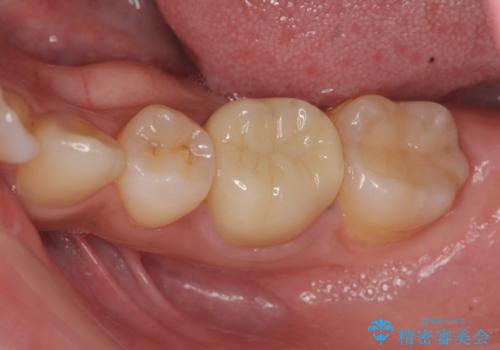

リアルな歯の色調にこだわるオールセラミッククラウン治療

- 歯の神経を除去したのちの、変色の改善を希望され来院されました。

再度根管治療を行ったのちの、オールセラミッククラン治療を計画します。

色調の再現に優れるオールセラミッククラウン スペシャルプランでの治療を希望されました。(保証5年間)

天然歯を再現したリアルな仕上がりに満足いただくことができました。

オールセラミッククラウン スペシャルプランは細やかな色調の再現に優れ、目立つ前歯の審美的な仕上がりがより達成されやすいプランです。